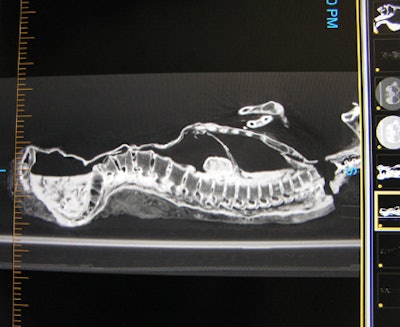

![]() |

| Above and below: 3D reconstructions from CT data of the mummy's head, scanned at 100 kVp, 100 mA, 750 msec rotation speed, 75 mAs, and a slice thickness of 0.5 mm. Images reconstructed using Vitrea 2 advanced visualization software (Vital Images, Minneapolis, MN). Images courtesy of Michelle Cotton, Advanced Radiology Consultants. |

The mummy also contained three to five "organ packets ... within the thoracic and abdominal regions" and "worn teeth from sand in the food," as well as a "huge opening into the cranial vault made to scramble the brains for removal" during the mummification process, according to Beckett. The mummy may even be from an older dynasty than was previously thought.